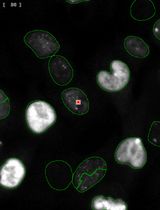

利用自动化图像细胞计数法简化量化p-γ-H2AX焦点分析,以评估暴露于FLASH辐射的小鼠黑色素瘤及黑色素细胞共培养中的DNA损伤

Streamlined Quantification of p-γ-H2AX Foci for DNA Damage Analysis in Melanoma and Melanocyte Co-cultures Exposed to FLASH Irradiation Using Automated Image Cytometry

SO Stefana Orobeti

ID Ioana Dinca

AB Alexandra Bran

IT Ion Tiseanu

FS Felix Sima

SP Stefana M. Petrescu

LS Livia E. Sima

2395 Views

Feb 20, 2025

In response to DNA-damaging physical or chemical agents, the DNA damage repair (DDR) pathway is activated in eukaryotic cells. In the radiobiology field, it is important to assess the DNA damage effect of a certain irradiation regime on cancer cells and compare it to the effect on non-transformed cells exposed to identical conditions. The first step in the DNA repair mechanism consists of the attachment of proteins such as the phosphorylated histone γ-H2AX (p-γ-H2AX) to DNA double-strand breaks (DSB) in the nucleus, which leads to the formation of repairing foci. Therefore, imaging methods were established to evaluate the presence of foci inside the nucleus after exposure to DNA-damaging agents. This approach is superior in sensitivity to other methods, such as the comet assay or the pulsed-field gel electrophoresis (PFGE), that allow direct detection of cleaved DNA fragments. These electrophoresis-based methods require high ionizing radiation dosages and are difficult to reproduce compared to imaging-based assays. Conventionally, the number of foci is determined visually, with limited accuracy and throughput. Here, by exploring the effect of laser-plasma accelerated electrons FLASH irradiation on cancer cells, we describe an image cytometry protocol for the quantification of foci with increased throughput, upon large areas, with increased precision and sample-to-sample consistency. It consists of the automatic scanning of fluorescently labeled cells and using a gating strategy similar to flow cytometry to discriminate cells in co-culture based on nuclei elongation properties, followed by automatic quantification of foci number and statistical analysis. The protocol can be used to monitor the kinetics of DNA repair by quantification of p-γ-H2AX at different time points post-exposure or by quantification of other DNA repair proteins that form foci at the DNA DSB sites. Also, the protocol can be used for quantifying the response to chemical agents targeting DNA. This protocol can be performed on any type of cancer cells, and our gating strategy to discriminate cells in co-culture can also be used in other research applications.